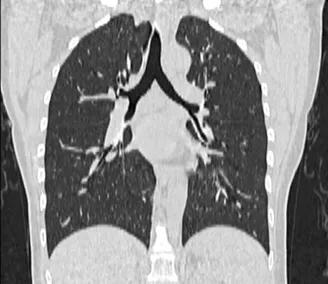

正常胸部CT图像

冠状位重建CT胸部图像